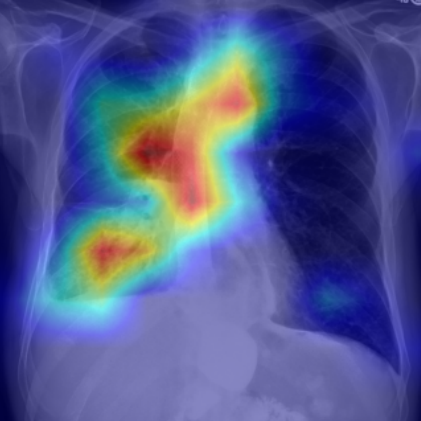

Refer to caption

Figure 4: Visualization of attention maps generated by PLAN on MS-CXR dataset. The red boxes indicate the ground truth for disease localization, while the heatmaps highlight regions with higher activation weights with disease-related phrases in the text.

IV-B1 Phrase Grounding

Phrase grounding associates textual phrases (e.g., disease descriptions or anatomical terms) with corresponding regions in medical images, offering precise diagnostic insights and enhancing model interpretability. Table II presents the phrase grounding results on the MS-CXR dataset. Using the Contrast-to-Noise Ratio (CNR) [27] as the evaluation metric, PLAN achieved the highest CNR across eight disease categories, outperforming MGCA and PRIOR. Heatmaps generated with Grad-CAM (Figure 4) further illustrate PLAN’s ability to accurately localize lesion sites and align disease-related phrases with image regions. Additional comparisons with baseline methods can be found in Figure 5. These findings highlight PLAN’s superior precision and interpretability in phrase grounding tasks.